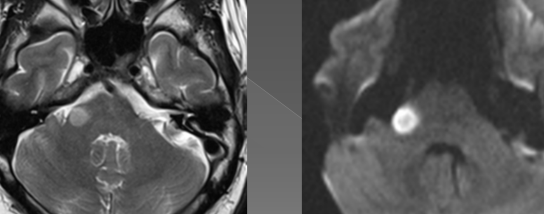

AVC fosse postérieure

!

Tumeur: Ependymome

Sep